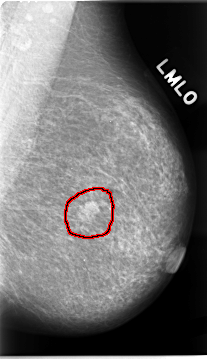

C_0023_1.LEFT_MLO

LEFT_MLO LINES 4656 PIXELS_PER_LINE 2680 BITS_PER_PIXEL 12 RESOLUTION 50 OVERLAY

FILE: C_0023_1.LEFT_MLO.OVERLAY

TOTAL_ABNORMALITIES 1

ABNORMALITY 1

LESION_TYPE MASS SHAPE LOBULATED MARGINS MICROLOBULATED

ASSESSMENT 5

SUBTLETY 5

PATHOLOGY MALIGNANT

TOTAL_OUTLINES 1

BOUNDARY